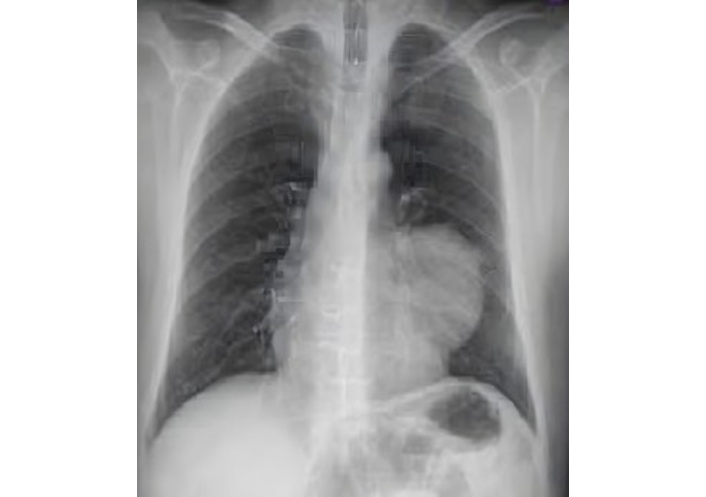

Cardiac enlargement and fractured left 2nd, 3rd, and 5th ribs were the important findings of chest X-ray (CXR) at first admission (Figure 2). Transthoracic echocardiography (TTE) and thoracic computed tomography (CT) confirmed a massive pericardial effusion (Figure 3). Cardiac valvular functions were normal. All of this indicated significant cardiac injury and ongoing cardiac tamponade. The diagnosis was confirmed once the pericardial cavity was accessed.

A TTE evaluation performed three months later did not report the mass seen on CXR as a possible pseudoaneurysm (Figure 4). The mass on the left side became more prominent on CXR (Figure 5), nineteen months later. A thoracic CT scan revealed a giant pseudoaneurysm on the posterior wall of LV which was 10 cm × 7 cm in size (Figure 6). The patient was urgently transferred to our center for definitive management, where a coronary angiography (CA) was performed. CA showed normal coronary anatomy (Figures 7 and 8), but left ventriculography confirmed the diagnosis: leakage of contrast medium into the pseudoaneurysm sac was clearly observed (Figures 9 and 10).